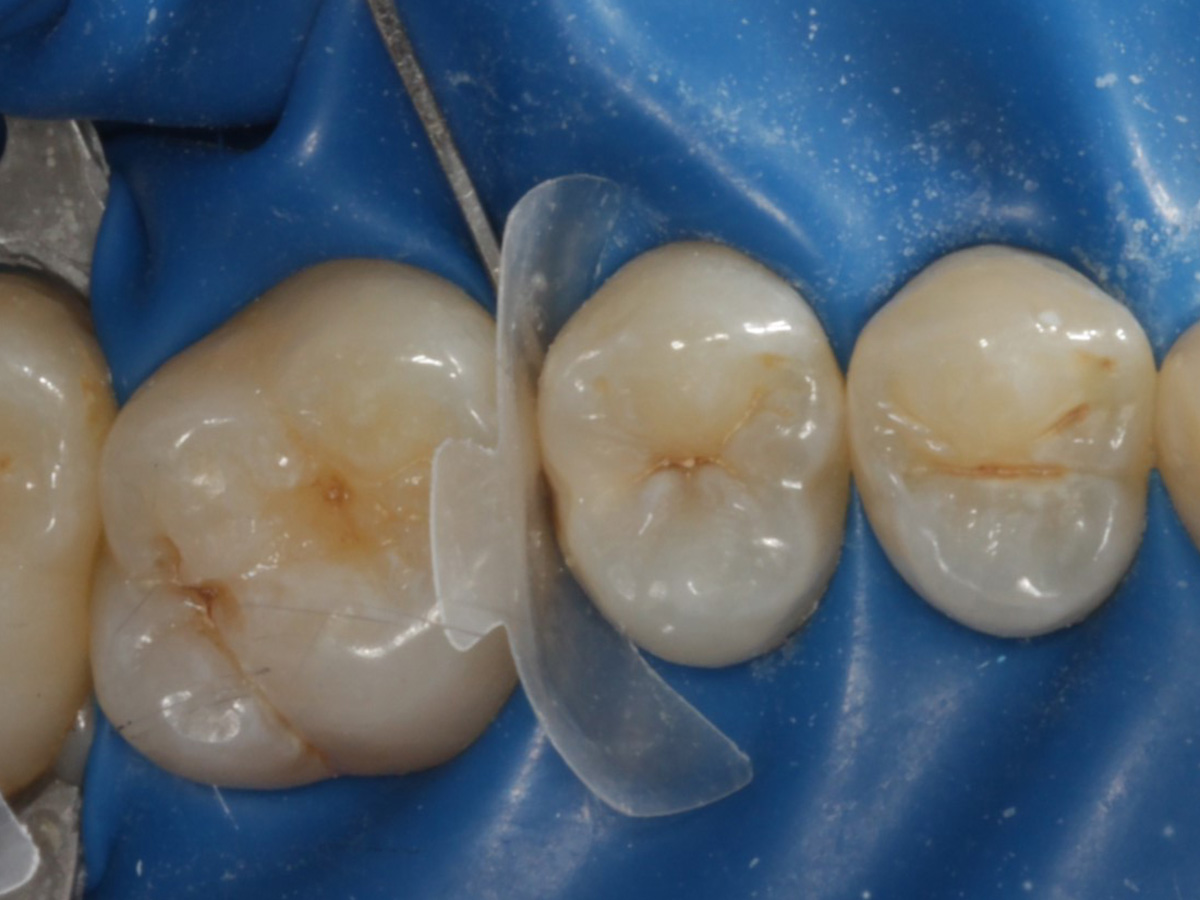

Abbildung 1

Approximalraumkaries an Zahn 25 distal